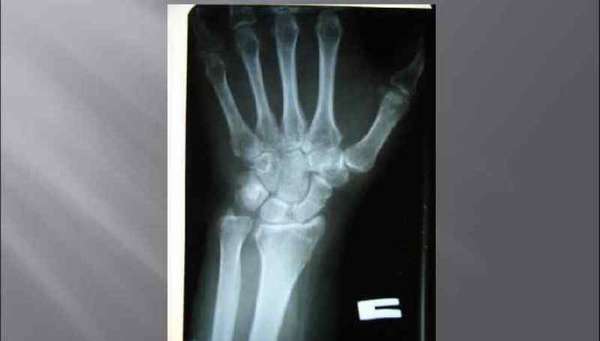

На первоначальном этапе врач собирает анамнез заболевания, в процессе беседы с пациентом уточняет обстоятельства падения и время. Далее производит осмотр, после которого пострадавший направляется на рентгенографию лучезапястного сустава в двух проекциях (прямой и боковой).

Для того чтобы оценить правильность срастания костных отломков, через неделю после травмы и перед снятием гипса назначают контрольную рентгенографию.